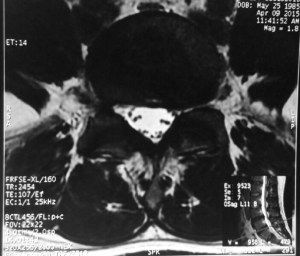

This is a patient who presented with sciatica in his left leg from a L5/S1 posterolateral left sided slipped disc in 2012.

He was offered surgery but chose conservative treatment.

His pain eventually resolved over a period of 3 to 6 months after taking medications and undergoing intensive physiotherapy.

The same patient underwent a new MRI scan of his lumbar spine in 2015 for lower backache. There was no sciatica in his lower limbs.

The MRI showed resorption of the previous large left sided slipped disc.